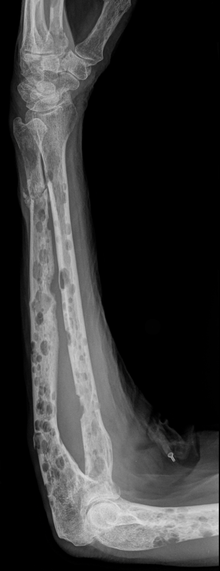

Kartais ortopedams tenka spręsti ir rimtesnes problemas, kai dėl įvairiausių sunkių ligų įvyksta patologinis kaulo lūžis. Tokius lūžius pastebėti ganėtinai sunku, tačiau kai tik pasiseka tai padaryti, reikėtų kuo skubiau kreiptis pas gydytojus – kad nebūtų per vėlu.